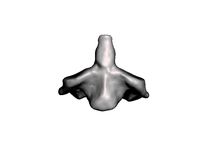

Second cervical vertebra axis

...del second cervical vertebra axis for download as obj and stl on turbosquid: 3d models for games, architecture, videos. (1617262)